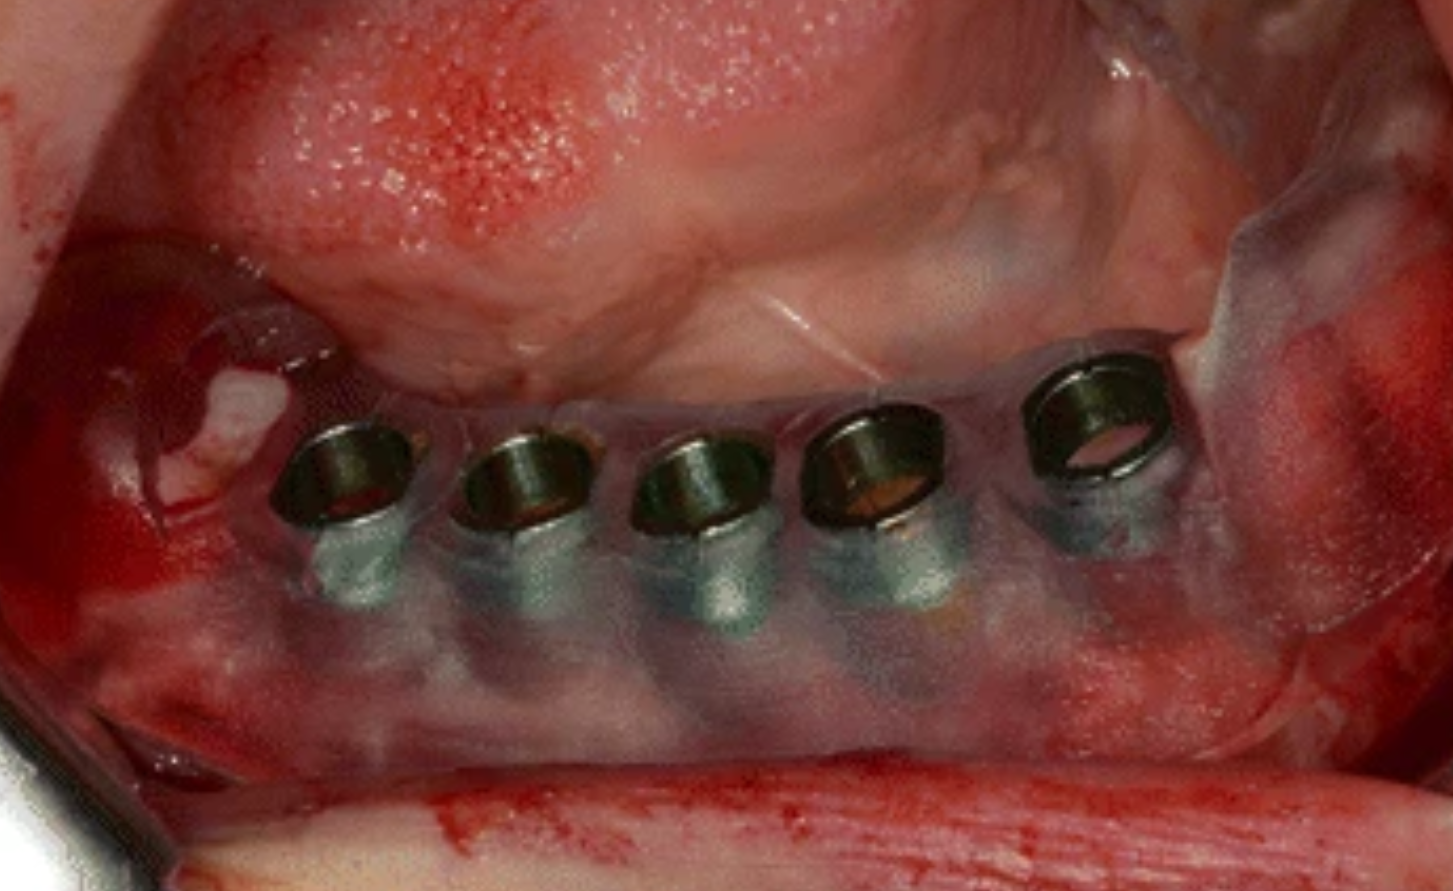

Fixed teeth in a day, also known as immediate load implants, is a procedure where dental implants and a temporary prosthetic are placed in a single visit.

This approach, often called All-OR-4 or All-on-6, allows patients to leave the clinic with functional teeth the same day. It is typically used for patients with significant tooth loss, providing an alternative to dentures by anchoring a full arch of teeth to 4-6 implants.

Surgical Placement

Precise placement of 4-6 implants under local anesthesia, typically 2-4 hours per arch using advanced guided techniques.